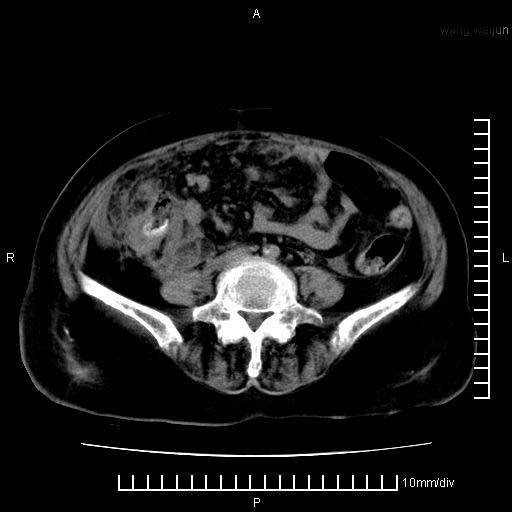

上腹疼痛月余,外院核磁诊断胰腺癌。现临床示右下腹可明显触及包块,可片子上怎么没有看到?

1.胰腺颈体部癌。

2。腹腔积液。

3。右胸腔积液,伴右肺下叶部分萎陷。

4。右肾盂囊肿。

胰腺体部癌累及周围器官,腹膜、粘连

1。胰腺ca伴腹膜腔转移

2。肝左叶低密度灶,考虑转移可能

胰腺体部癌累及周围器官,腹膜、粘连,临床摸到的可能是粘的组织

胰腺结构模糊,胰尾部见囊性包块,周围脂肪密度增高,左肾前筋膜增厚,胸水、腹水。不符合胰腺ca伴腹膜腔转移。考虑胰腺炎伴假性囊肿形成、胸腹腔积液。

右肾盂囊肿。

1)考虑胰腺癌并胰腺假性囊肿形成。2)肝内低密度灶,不排除转移。3)右肾盂积水。4)腹水。5)右侧胸腔积液并右肺下叶部分膨胀不全。

考虑胰腺ca伴腹膜腔转移、肝左叶转移、右肾积水。右胸腔积液。